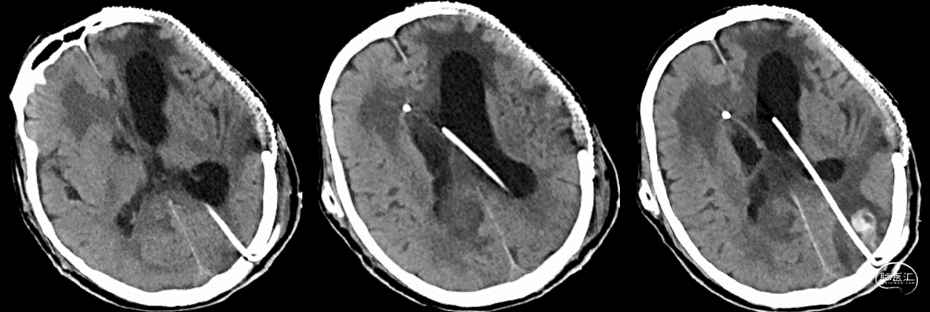

入院查体:体温:37.0℃,呼吸:16次/分,脉搏:69次/分,血压:144/93mmHg;意识不清,GSC评分:3+T+4,右侧后枕部手术切口稍红,局部可见水疱样隆起,余头部手术切口愈合可,右侧V-P分流阀下压及回弹良好,双侧瞳孔等大等圆,直径3.5mm,对光反射灵敏,颈抵抗阳性,双肺呼吸音粗,可及少量痰鸣音,心律齐,未及明显杂音。腹部手术切开愈合可,腹肌紧张,压痛可疑,四肢肌力查体不配合,刺痛时可及肢体回缩,肌张力增高,双侧巴氏征阳性。辅助检查:2021-9-6我院头颅CT提示:开颅血肿清除+去骨瓣减压术及颅骨修补+V-P分流术后改变,脑积水(图1);胸部CT提示:两肺下叶渗出伴少许积液,心脏增大伴少许心包积液,右侧第3-9肋骨骨痂形成,右侧肩胛骨骨折。腹部CT提示胃肠壁水肿,脂肪间隙浑浊。

图1. 2021-9-6我院头颅CT提示:开颅血肿清除+去骨瓣减压术及颅骨修补+V-P分流术后改变,脑积水。根据患者病史、临床症状及影像学表现,诊断为:1.发热待查:肺部感染?腹腔感染?颅内感染?2.脑积水V-P分流术后;3.重型颅脑损伤,左侧开颅血肿清除+去骨瓣减压术后;4.左侧颞骨骨折;5.右侧肩胛骨骨折;6.右侧肋骨骨折;7.骨盆骨折内固定术后。入院后完善常规及相关检查,予“头孢哌酮舒巴坦 2g q8h+利奈唑胺0.6g q12h”经验性抗感染、脱水降颅压、雾化化痰、预防癫痫、控制呃逆等对症处理。于2021-9-7行腰穿检查,测得初压为90mmH₂O,脑脊液化验正常。考虑患者脑积水明显,可能存在分流管不通畅情况,于2021-9-8行分流泵储液囊穿刺外引流处理后,患者意识较前好转,自主睁眼增多。2021-9-10储液囊穿刺部位附近有外渗,予换药处理。于2021-9-11拔除穿刺外引流装置,复查头颅CT(图2)提示脑积水较前好转。